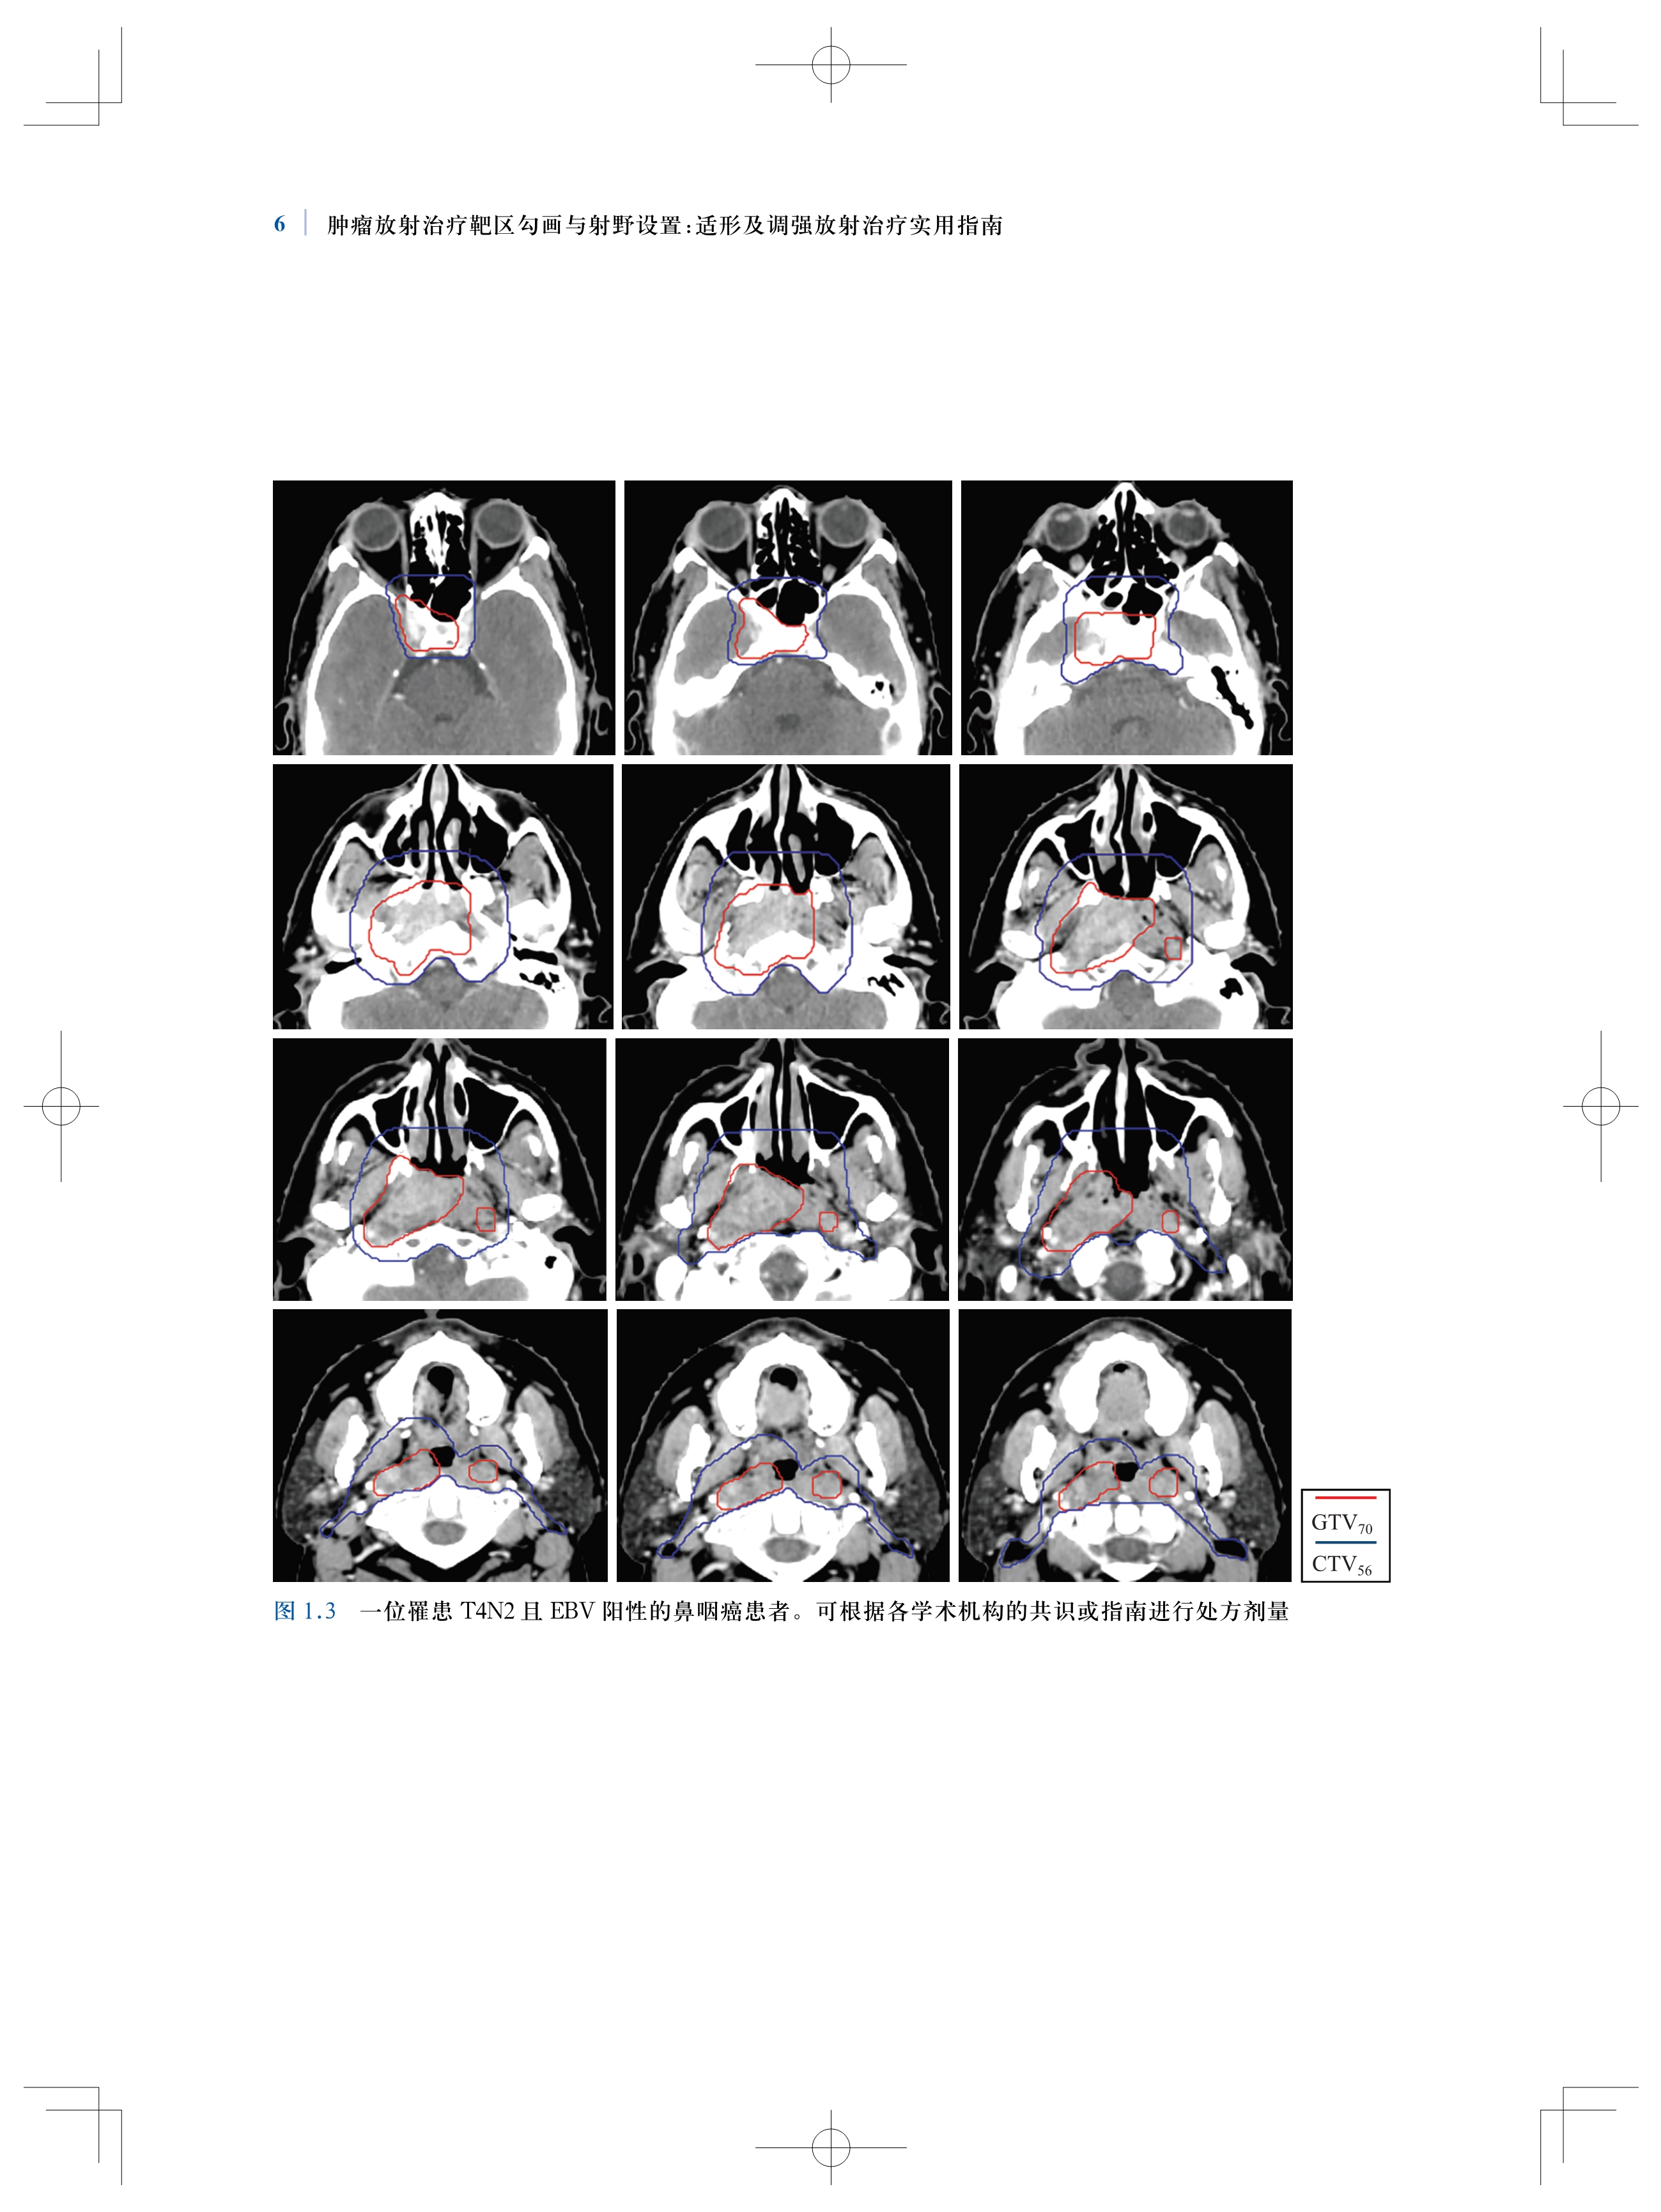

书名:肿瘤放射治疗靶区勾画与射野设置:适形及调强放射治疗实用指南(原著第2版)